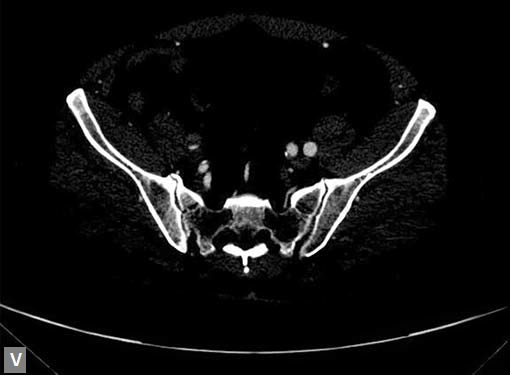

Connective tissue disease, hypertension and iatrogenic (Figs 19K to L) injury are the common causes for dissection. Radiologist not only establishes the diagnosis, also evaluates the extent of dissection, presence of thrombosis particularly in false lumen. In case of type A dissection, involvement of aortic root is determined. Relation of thrombosed lumen and ostia of coronary vessels, cephalad branches (Figs 19N, R to V) of aorta is determined. Most of the occasions membrane is demonstrated. Spiral nature of the membrane can be seen

Double barrel appearance is seen on coronal and sagittal

images. Type B dissections can extend even to common

iliac arteries bilaterally. Superiorly it can extend to involve

common carotid and vertebral arteries.

Figs 19A to Y (A to C) Scannogram (A), plain (B) and contrast study (C) show partial anomalous pulmonary venous connection; (D to F) Heterotaxy; (G) Aortic occlusion; (H and I) Aortic stents; (J) Aortic dissection with ‘Benz’ sign due to second dissection within the true lumen; (K, L and M) Aortic dissection with thrombus in pseudolumen following catheter angiogram; (N) Aortic dissection involving common carotid arteries and subclavian artery; (O, P, Q and R) Aortic dissection with right renal artery arising from true lumen and left renal artery from false lumen; (S, T, U and V) Stanford B dissection with extension Y to iliac vessels; (W to Y) Aneurysmal dilation of ascending aorta